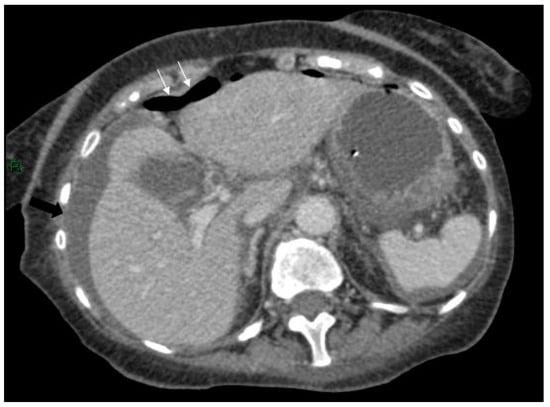

A 72-year-old female attended for a laparoscopic cholecystectomy on the background of severe gallstone pancreatitis four weeks previously. Examination prior to her operation revealed that she had an upper abdominal mass. The procedure was cancelled, and computed tomography (CT) was performed. This revealed a pseudocyst with three components—a large 16 × 12 cm thin-walled cyst in relation to the head, body and proximal tail of the pancreas, a separate 6 cm cyst in the distal tail, and a 10 × 5 cm cyst in the area of the transverse mesocolon compressing the transverse colon (Figure 1 and Figure 2).

Figure 2.

Axial post-contrast CT scan of the upper abdomen showing the inferior aspect of the cyst with bi-lobed appearance (arrows) in the pelvis.